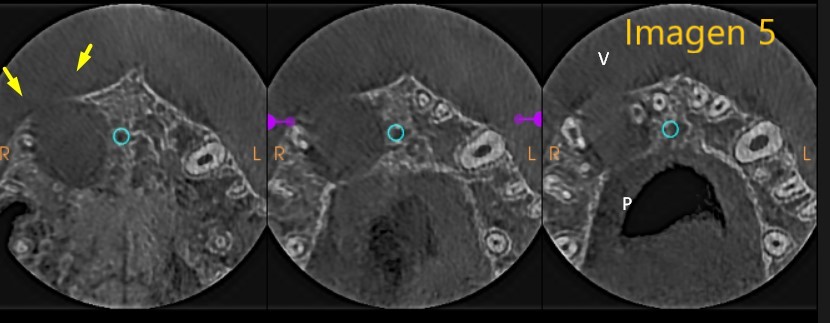

-         También podemos observar que la expansión de dicha lesión se extiende por y hacia cara vestibular – palatino y hacia piso de fosa nasal derecha, llegando a provocar perdida de tabla ósea alveolar, tanto vestibular como parte palatina. Ver Imagen 5.